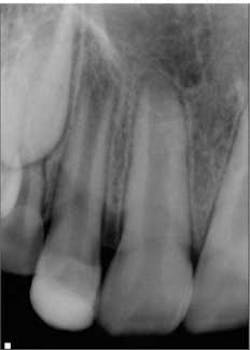

So how is the environment re-created? Let’s look at a case. Fig. 1 shows a lateral incisor that had sustained a concussive injury with an uncomplicated crown fracture. This 10-year-old boy presented to the office with complaint of pain, and swelling was present in the buccal vestibule. The tooth was diagnosed as having pulpal necrosis and an acute apical abscess. Due to the presence of an apical radiolucency and an immature apex, the regenerativeprotocol was chosen.Fig. 1: Tooth No. 7 showing incompletely formed apices and apical periodontitis. The patient also presented with pain to percussion and swelling.